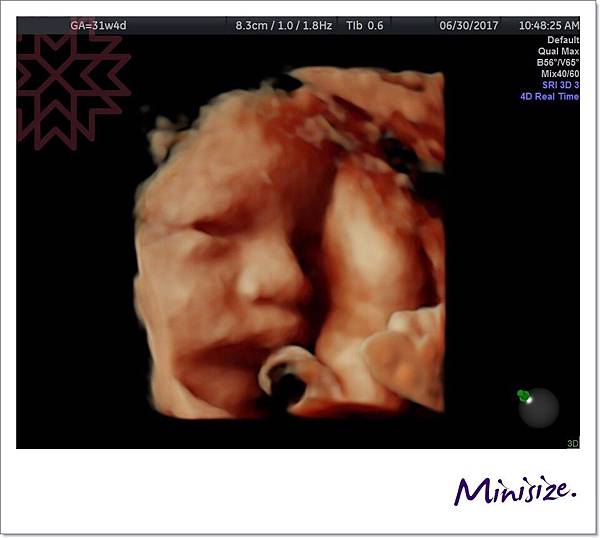

31週時

第一次看到Timo睜開雙眼

經驗豐富的醫生也驚嚇地說她很少看到寶寶眼睛張這麼大

後來 Timo又躲起來

醫生搖肚皮搖好久後

正當麻麻跟醫生、護士聊天

說到寶寶好像都知道產檢的時候會被超音波偷拍

不想要自己的隱私被打擾!

麻麻還說是偶像包袱嗎?

Timo立馬用「偷瞪」的表情回應我們

哈哈哈哈哈

這怪表情把我們都逗樂了~

最後

Timo秀出愛睏想睡覺的表情

我們就不打擾他了